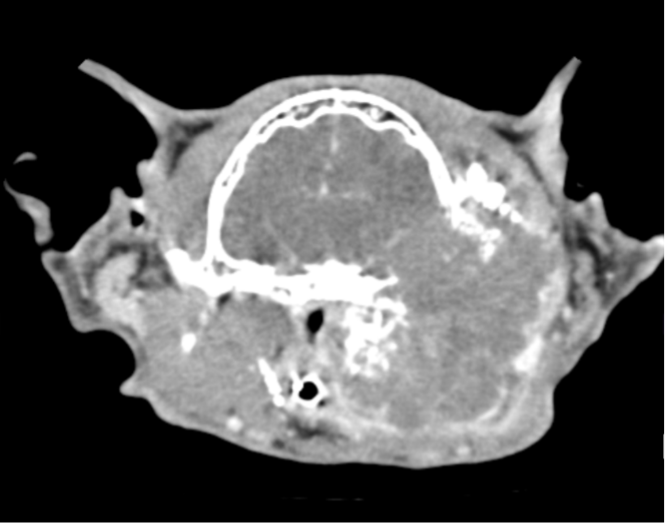

Thinking of buying this advanced imaging technology for your general-practice veterinary hospital? A veterinary imaging specialist answers the money, time and space questions.